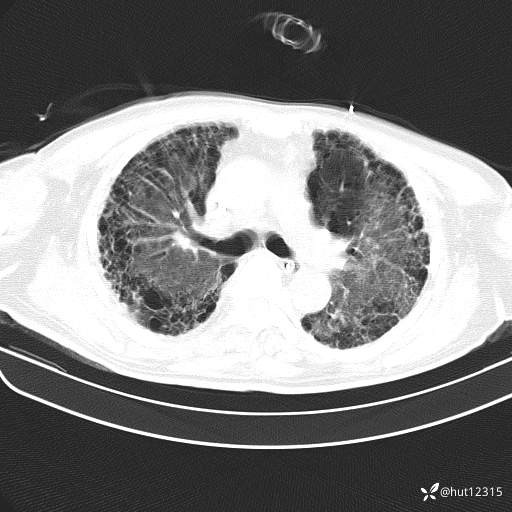

CT:肺纤维化并感染

2.特发性肺纤维化并重症肺炎,ARDS